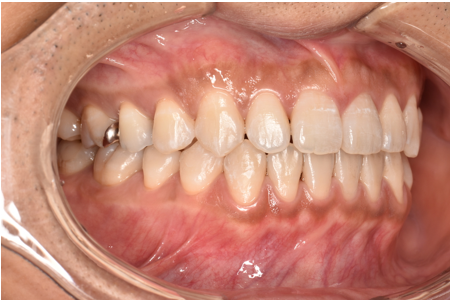

治療前

| カウンセリング・診断結果 | 診察したところ、上の前歯の真ん中に隙間が空いている状態でした(正中離開)。 |

| 行ったご提案・治療内容 | CTや3Dスキャンでの精密検査の結果、奥歯の噛み合わせ等には大きな問題はありませんでした。 そのため、インビザラインライトでの治療をご提案しました。 |